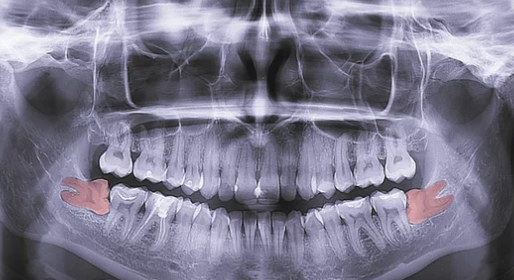

1) 발치 전 준비

- 치과 상담: X-ray 촬영으로 사랑니의 위치, 매복 상태, 주변 신경과의 관계를 확인합니다.

- 진단: 사랑니의 발치 필요성을 결정하고 발치 방법(일반 발치, 수술적 발치)을 계획합니다.